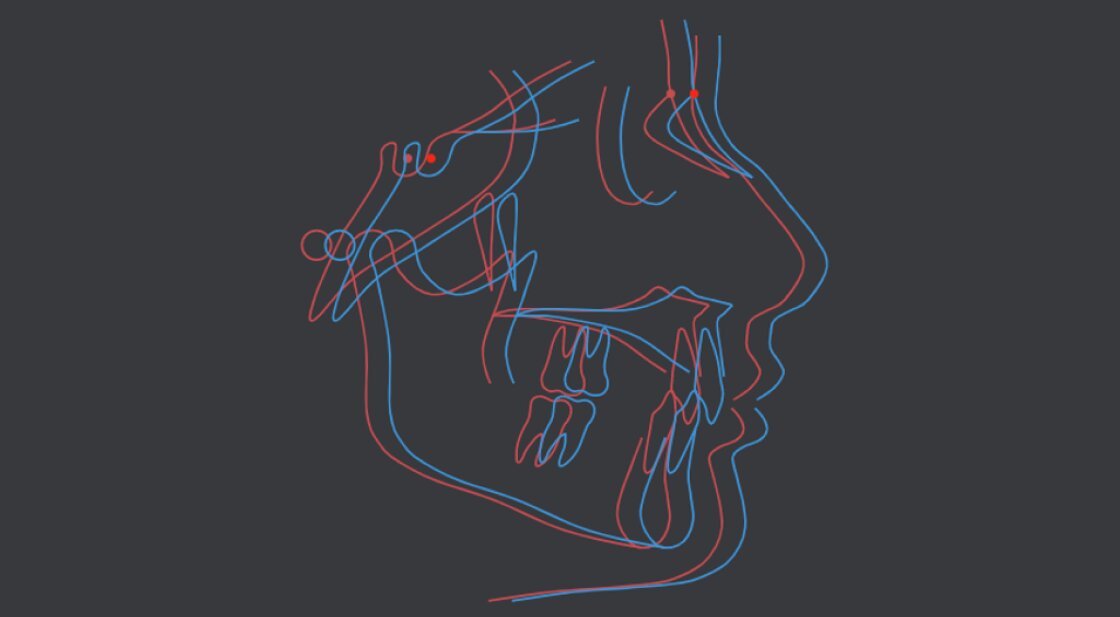

Superimposition

Our Intelligent Cephalometry System uses advanced algorithms and machine learning to ensure that the superimposition process is accurate and precise. This feature helps orthodontists evaluate treatment progress and make necessary adjustments to the treatment plan.